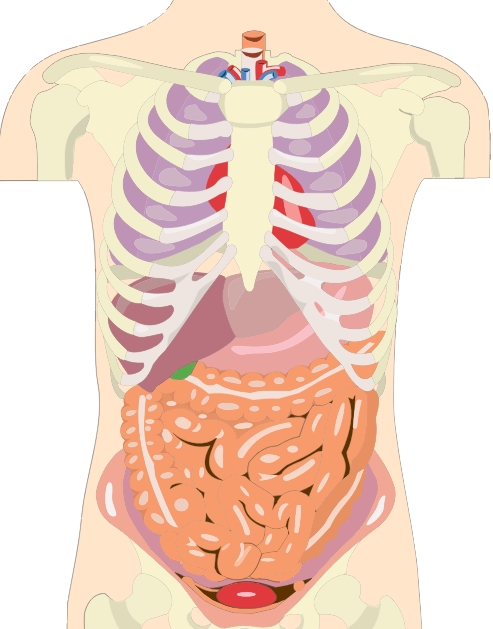

소장이나 대장 일부에서 여러 원인으로 인해 부분적으로나 또는 완전히 장의 일부가 막혀서 장 속에 있던 음식물과 소화액, 가스 등의 내용물이 배 안에서, 장 속에서 축적되면서 장애를 일으키게 됩니다. 이것을 장염전, 장폐색, 장꼬임이라고 합니다. 물론 그 꼬인 부분의 증상 정도에 따라 이름을 달리 부를 수도 있습니다.

장꼬임 생긴 부분에서의 통증으로 시작되어 복부 전체로 통증이 퍼지게 되는데 여기에 가스 등이 차면서 복부팽창, 복부팽만이 발생할 수 있습니다. 그리고 복통에 동반된 구토 등으로 탈수 증상이 생길 수 있습니다.